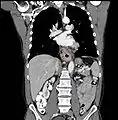

إن أفضل الطرق لتشخيص المرض هي عن طريق التنظير الباطن العلوي حيث يمكن رؤية الورم بشكل مباشر وأخذ خزعات من المناطق المصابة وفحصها مخبرياً، كما يمكن استخدام عدة فحوصات شعاعية للمساعدة في تشخيص المرض وتحديد مدى تغلغل الورم وانتشاره، من أهم تلك التقنيات: التصوير الطبقي المحوري و وجبة الباريوم, وقد يتم إجراء اختبار حركية المريء لاستبيان تضرر عضلات المريء بسبب السرطان.

معرض صور